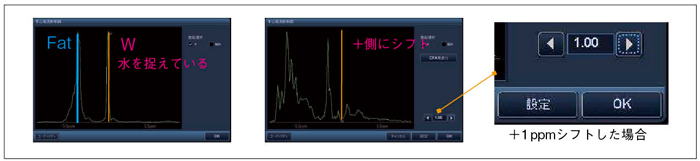

中心周波数 Mri

核磁気共鳴画像法 Wikipedia

2013 226388号 磁気共鳴イメージング装置及び磁気共鳴イメージング方法 Astamuse